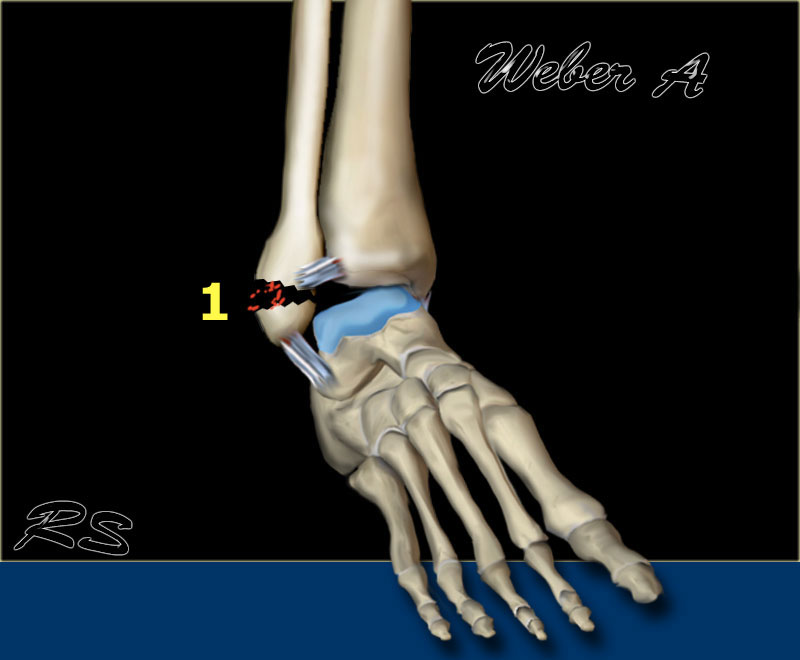

Stage 1

Các hình ảnh cho thấy gãy xương loại Weber A điển hình.

Tất cả đều là gãy xương giai đoạn 1.

Giai đoạn 2 cực kỳ hiếm gặp.

Chú ý hướng nằm ngang của các đường gãy.

Đây là các gãy xương kiểu giật đứt do kết quả của sự bong gân giật.

Stage 2

Giai đoạn 2 không phổ biến và dễ phát hiện.

Lực khép lớn hơn dẫn đến mắt cá trong bị đẩy ra theo chiều dọc hoặc chéo.

Giai đoạn 2 không vững vì vòng cổ chân bị gãy ở hai vị trí.

Lưu ý hướng nằm ngang của gãy mắt cá ngoài và hướng thẳng đứng của gãy mắt cá trong.

Những lực cực lớn hẳn đã đẩy bật mắt cá trong ra.